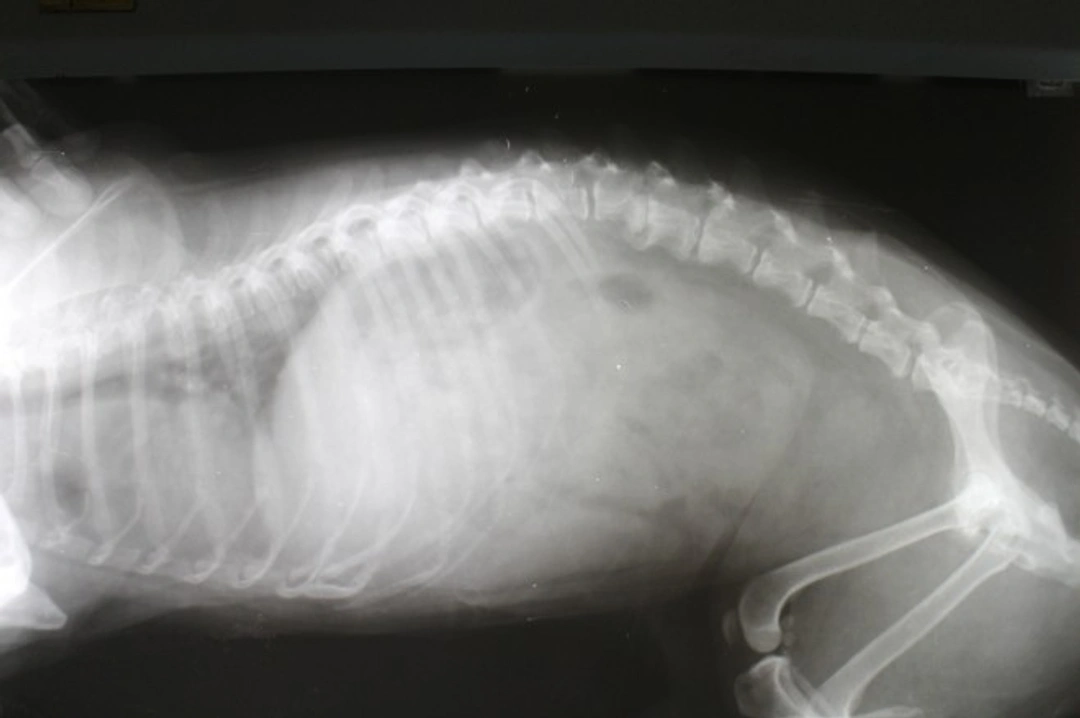

X-rays are invaluable for detecting a wide range of conditions. They provide clear images of bones, such as fractures or abnormalities, and can identify swallowed foreign objects, bladder stones, and certain tumours. X-rays also help assess enlarged organs like the heart or liver, which may indicate disease. Additionally, vets use x-rays to monitor pregnancy by counting puppies inside expecting bitches.

However, x-rays have limitations when it comes to soft tissues like ligaments or some organ details. In such cases, your vet may recommend ultrasound or MRI for more detailed imaging.